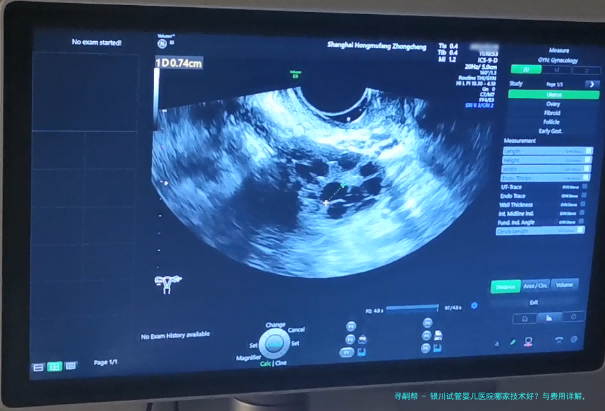

是动态数据,受患者岁数、病因、胚胎质量等多要点影响。银川主要生殖医学中心的临床妊娠率(移植后经B超认定怀孕的比率)在40-55之间,符合国内平均水平。宁夏医科大学总医院和银川市妇幼保健院因其例子量大、技术安定,统计常处在地区前线。但务必理解,是统计观点,个体情况需详细解析。